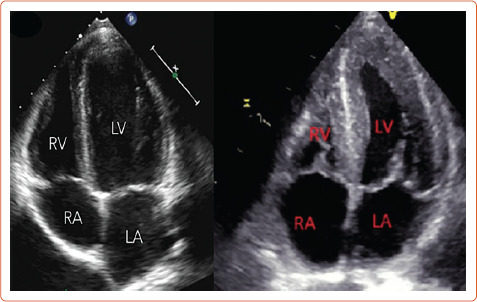

肥胖症日益流行,对妊娠构成了重大风险。代谢损伤可能与短期和长期的孕产妇和围产期发病率和死亡率有关。人们已经知道妊娠期外代谢紊乱对心血管的影响,但对肥胖并发妊娠的心脏功能却知之甚少。孕产妇的心脏适应性在正常妊娠中起着至关重要的作用,而且已知与不良妊娠结局的病理生理学有关。减肥手术是最成功的可持续减肥治疗方法,孕前减肥手术可极大地改变孕产妇的代谢状况和妊娠结局。在这篇综述中,我们将讨论受肥胖影响的妊娠及其相关的妊娠糖尿病和高血压(妊娠期慢性和高血压疾病)后果以及减肥手术后妊娠的母体心脏功能方面的现有证据。

The obesity epidemic is growing and poses significant risks to pregnancy. Metabolic impairment can be associated with short- and long-term maternal and perinatal morbidity and mortality. The cardiovascular implications are known in those with metabolic disorder outside of pregnancy; however, little is known of the cardiac function in pregnancies complicated by obesity. Maternal cardiac adaptation plays a vital role in normal pregnancy and is known to be involved in the pathophysiology of adverse pregnancy outcomes. Bariatric surgery is the most successful treatment for sustainable weight loss and pre-pregnancy bariatric surgery can drastically change the maternal metabolic profile and pregnancy outcomes. In this review, we discuss the available evidence on maternal cardiac function in pregnancies affected by obesity and its associated consequences of gestational diabetes and hypertension (chronic and hypertensive disorders in pregnancy), as well as pregnancies following bariatric surgery.